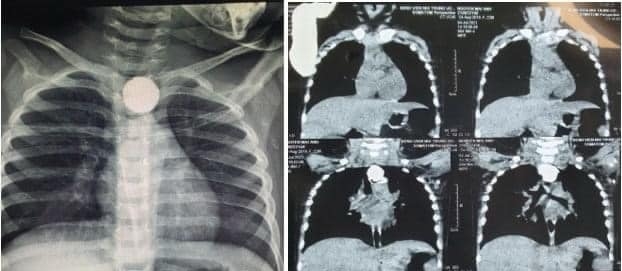

5.Em bé rò khí thực quản do nuốt phải pin

Em gái 22 tháng tuổi ở Thái Bình bị ho, khò khè, bác sĩ phòng khám tư kê đơn thuốc về nhà uống song tình trạng bệnh không thuyên giảm

Hình ảnh dị vật cản quang hình tròn nằm tại thực quản ngực Bệnh nhi. Ảnh: Bác sĩ cung cấp